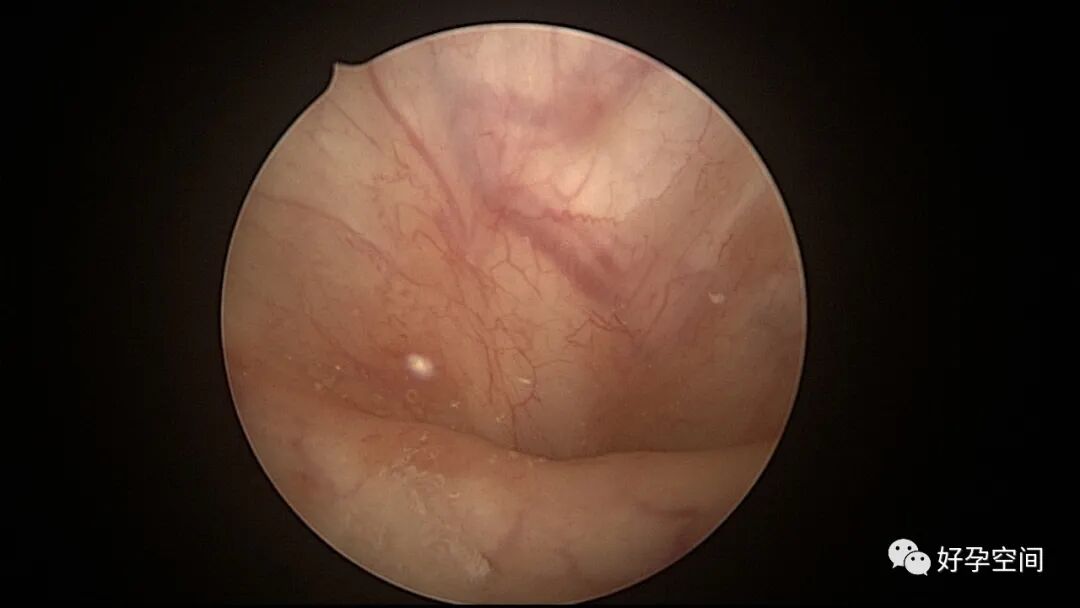

病例3:(病人年龄及取卵个数不详)取卵术后血尿膀胱内血块尿潴留,膀胱灌洗效果不佳,宫腔镜探查膀胱,清除血块,膀胱多处穿刺伤,电凝止血。

病例4:32岁,取卵13枚,取卵术后血尿膀胱内血块尿潴留,膀胱灌洗效果不佳,宫腔镜探查膀胱,清除血块,膀胱底见穿刺伤,电凝止血。